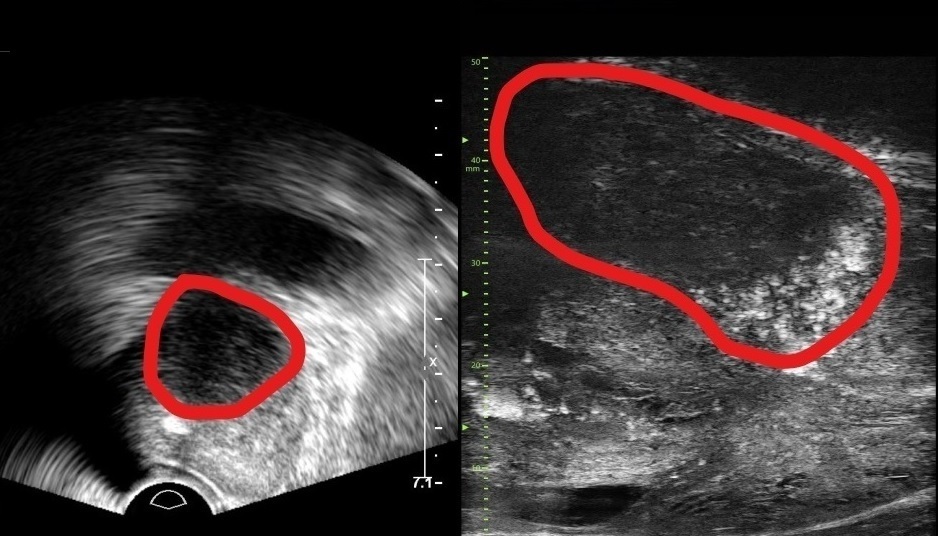

남성 난임 원인과 치료 방향 스트레스·환경 호르몬 등 복합적 영향 5년간 남성환자 37% ↑… 조기검진 필요...